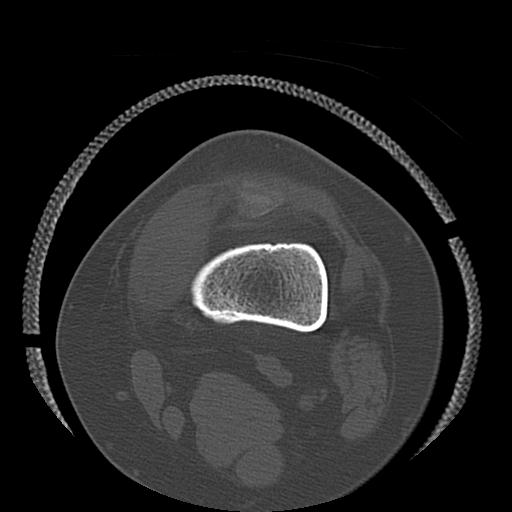

56476 8/28 4R 1/21 2R 左足関節 デジカメ写真 72歳女性 右足関節AS

102755 1/4 2R 1/15 2R 右足関節 68歳女性 右三果脱臼骨折